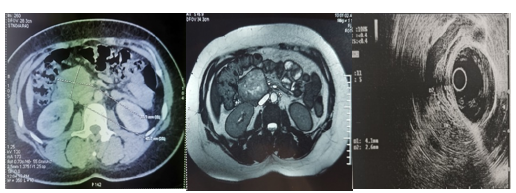

Solid Pseudopapillary Tumor of the Pancreas: A Case Report

Lamara Abdelhak, Medjahdi Sid Ahmed, Gadda Mounir, Boukhane Mohamed, Nahida Harchouche, Bloulou Mamed Lamine, Saadna Adlene and Selmani Khaled. 6(7): 12-18.